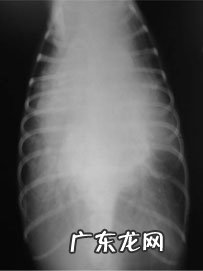

胸骨X线检查

胸骨X线检查:胸骨内影像总体相对密度上升 , 心血管轮廊没法辨别 , 提醒很有可能存有胸腔积水;支气管上抬 , 与腰椎平行面 , 提醒心血管很有可能存有显著扩大;肺泡动静脉增大增粗 , 提醒血肿 , 气体支气管炎征提醒支气管型外渗 。综合性之上信息内容猜疑心力衰竭造成胸腔积水和急性肺水肿 , 可根据超声心动查验确定心肺功能及变病种类 。